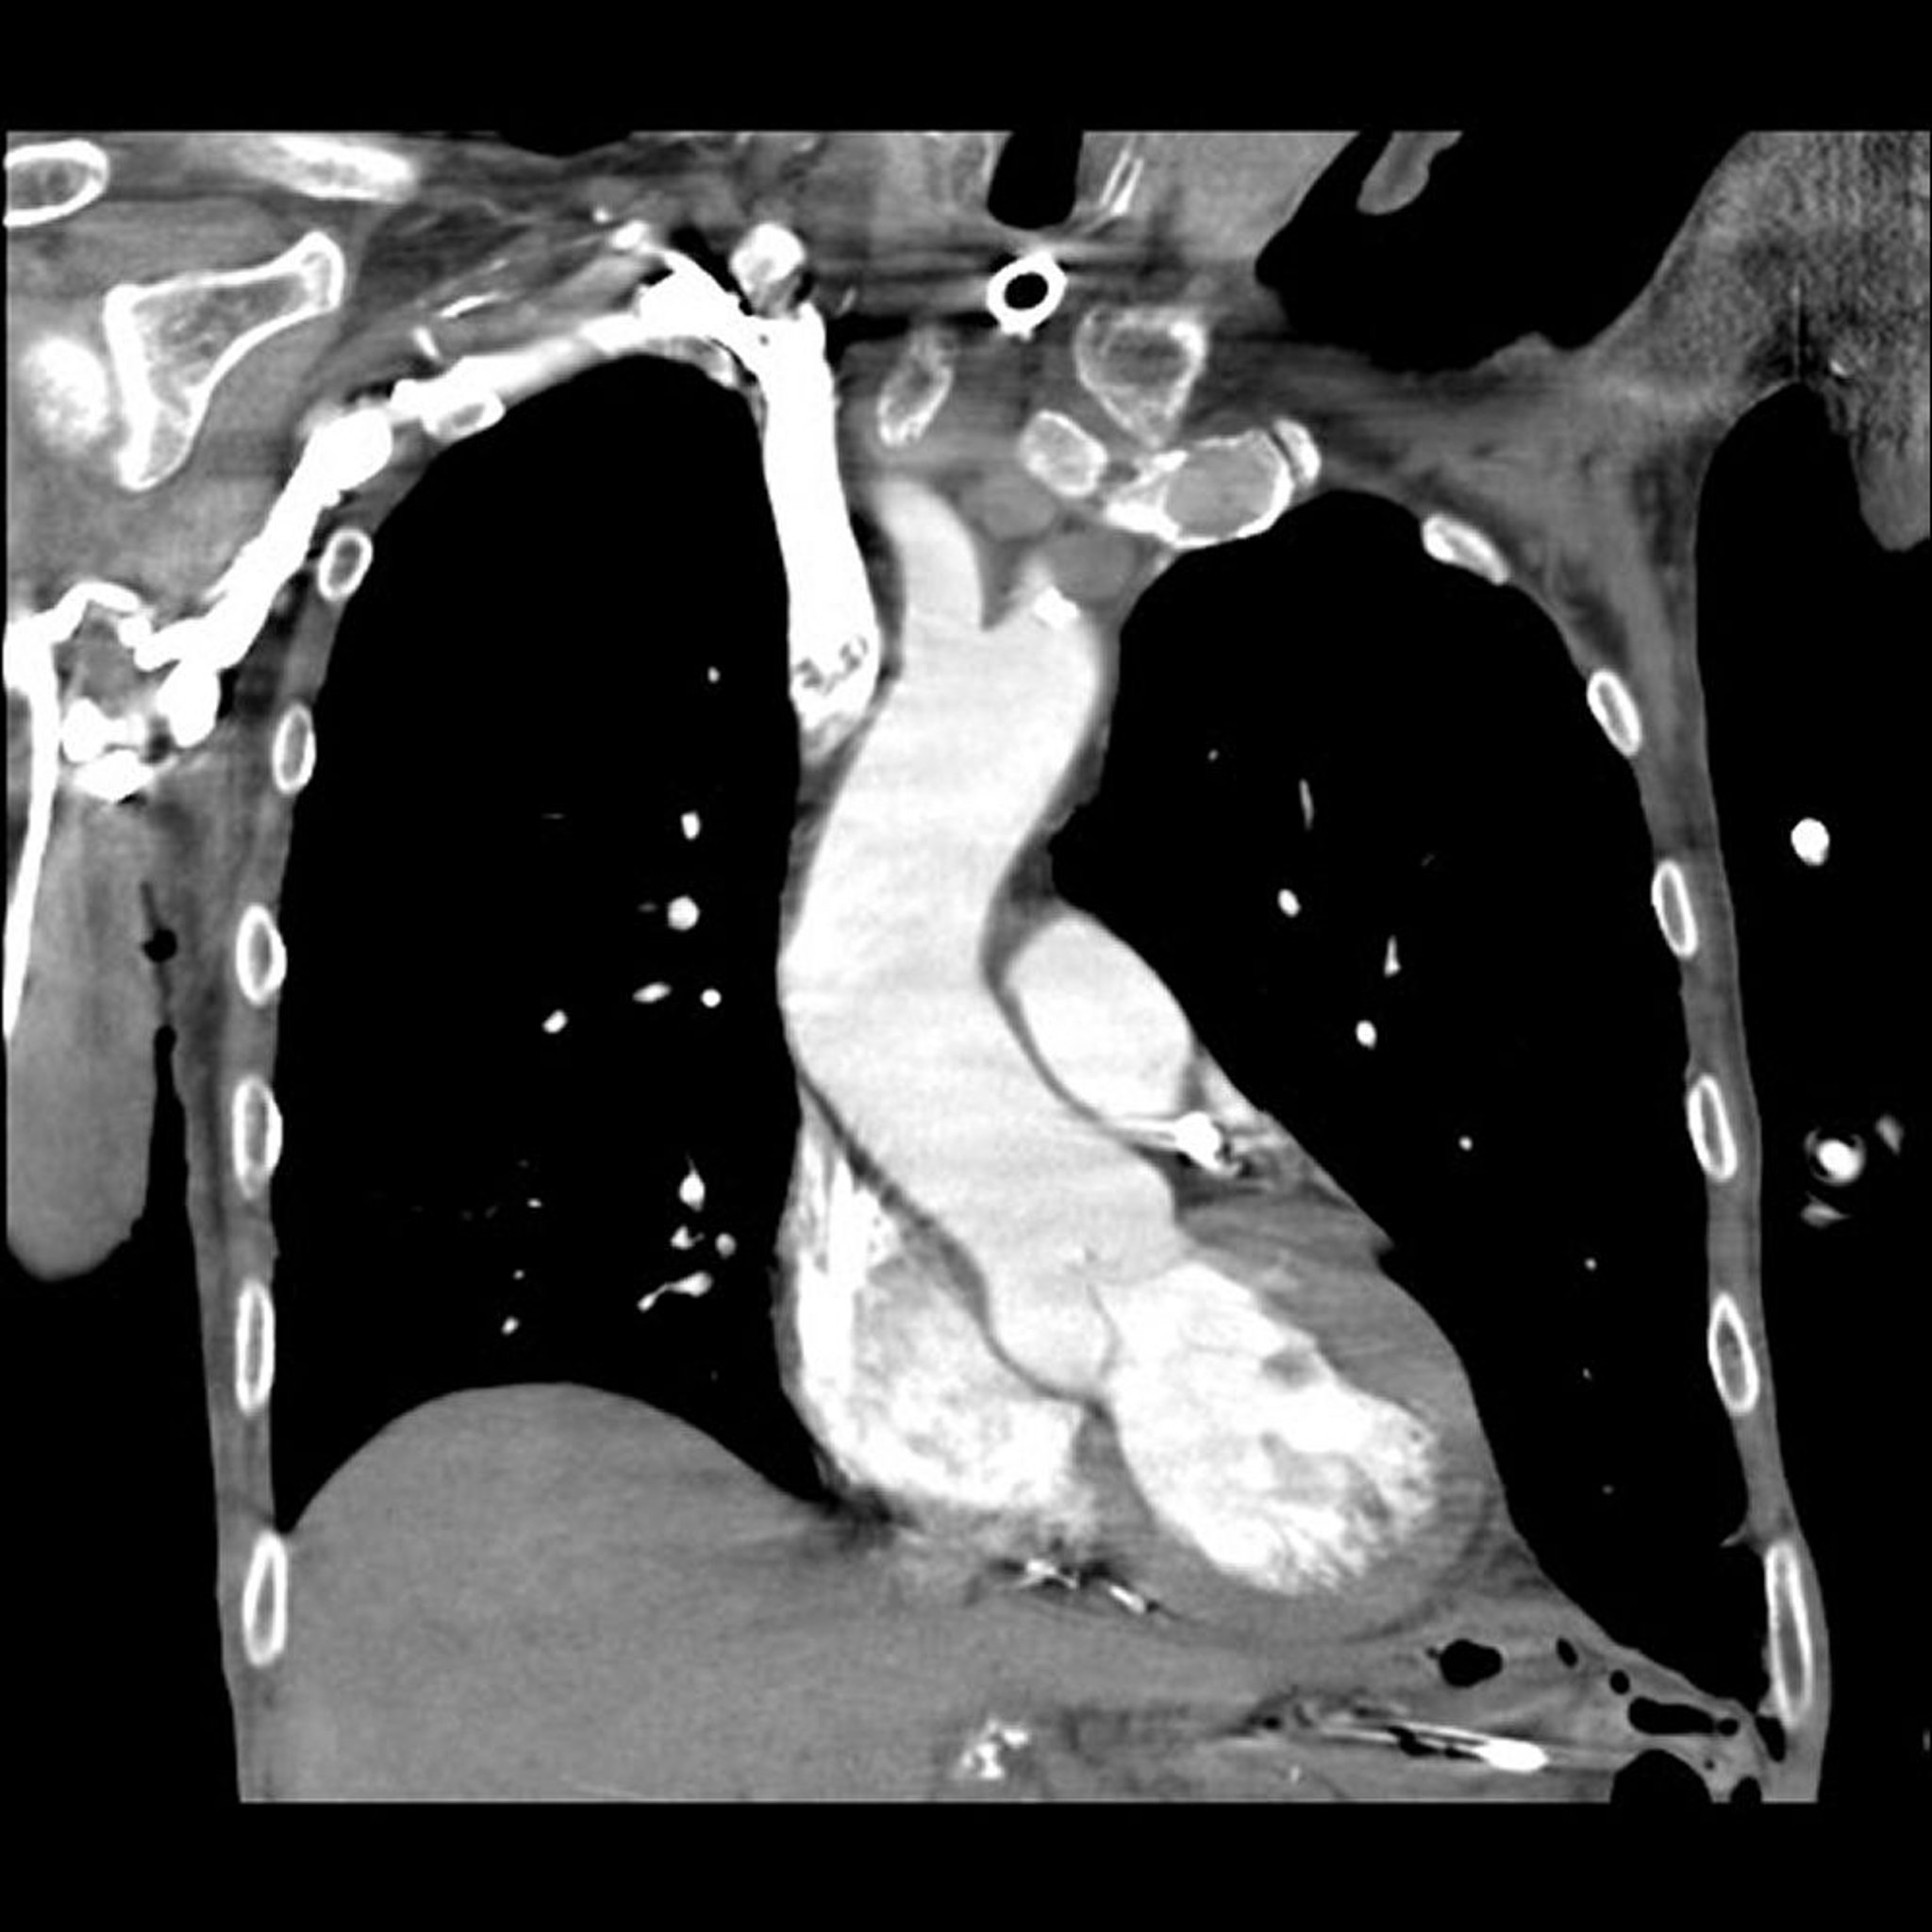

컴퓨터 단층촬영(CT) 폐 혈관조영술

이미지 제공: 의학박사 Mehmet Kocak